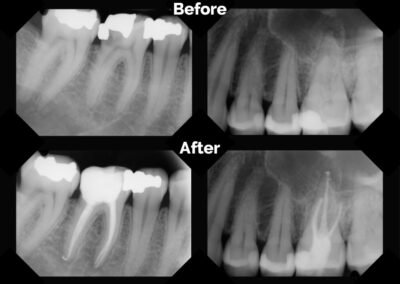

In some cases, a decayed or infected tooth may require a root canal to remove the pulp. If a root canal goes untreated, it may lead to an abscess, swelling, and potential bone loss, resulting in a costly procedure.

Don’t suffer through tooth decay or infection. Dr. Fonseca provides root canal procedures for our patients. Our team guides you through the procedure, beginning with a consultation appointment and post-appointment instruction.

Following the root canal, you will be asked to schedule a follow-up appointment. During this appointment, our team will inspect the teeth in question, follow the progression of your healing, and answer any questions you may have.